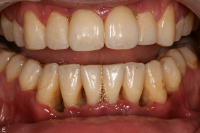

En bakteriellt orsakad inflammation som leder till en progressiv förlust av tändernas stödjevävnader.

Diagnostik

Det viktigaste måttet att påvisa sjukdom i parodontala vävnader är blödning.

• Gingivit blödning vid sondering, ingen benförlust, fickdjup 3 mm eller mindre. Parodontitis superficialis: fickdjup 5 mm eller mindre, horisontell och/eller angulär benförlust mer än 2 mm och blödning/pus vid sondering.

• Parodontitis profundus fickdjup 6 mm eller mer, horisontell och/eller angulär benförlust mer än 2 mm och blödning/pus vid sondering.